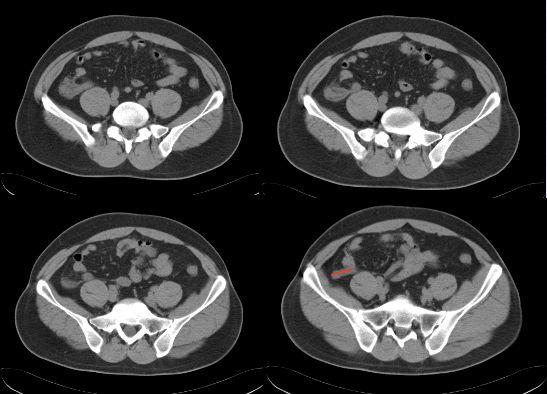

ct片上总是找不到阑尾3步法教你快速定位

急性阑尾炎的ct表现

【经典之作】正常阑尾和阑尾炎的ct表现

急性阑尾炎ct诊断

全面讲解正常阑尾和阑尾炎的ct表现